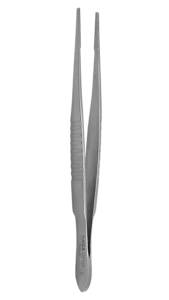

Our innovative, single-use tissue forceps come in a wide tip size range, ranging from 0.10mm to 0.50mm, and different shaft and handle shapes, platforms, and notches. With our wide variety of ophthalmic surgery instruments, you can rest assured that you will find the tissue forceps perfect for your eye surgeries. You can choose between curved shafts and angled shafts, flat, round knurled, castroviejo, round, and serrated handles, with or without tying platforms and notches. Designed by surgeons, specifically for your comfort. You can choose from some of our models, such as Moorfield forceps, Gillis Tissue forceps, and Adson forceps. With this range of fixation forceps, you can enjoy peace of mind in the operating room.

551235 - Moorfields Forceps